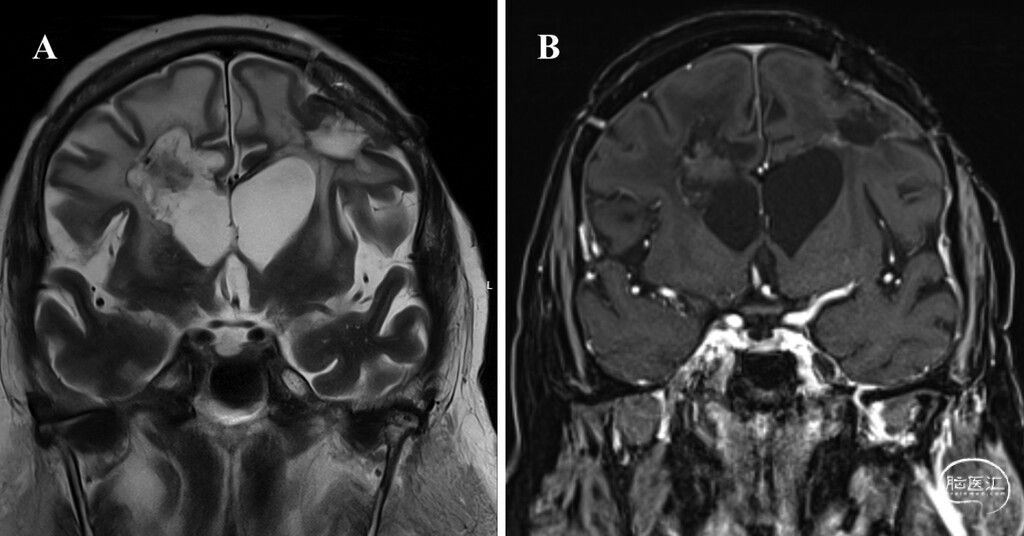

● 病例1:患者为71岁女性,因记忆力减退、言语紊乱就诊。MRI检查显示为多灶性病变,其中左侧额叶见一大小约37×33×32毫米的不均匀强化肿块,右侧脑室旁见一大小约37×28.8×25.5毫米的病灶并累及胼胝体(图1)。考虑到患者年龄及需要避免多次开颅,神经肿瘤多学科会诊建议采用同期混合手术方案:先对左侧额叶病灶进行开颅切除,随后立即对脑室旁病灶实施LITT。

图1:病例1术前MRI,示多灶性GBM。A:轴位增强T1加权像显示左侧额叶有一不均匀强化肿块,右侧脑室旁肿块延伸至胼胝体。B:冠状位增强T1加权像显示左侧额叶不均匀强化病灶伴中央坏死,右侧脑室旁肿块累及胼胝体前部。C:冠状位T2加权像显示多灶性肿块,包括累及右侧胼胝体前部及脑室旁区域的病灶,以及左侧额叶伴瘤周水肿的肿块。